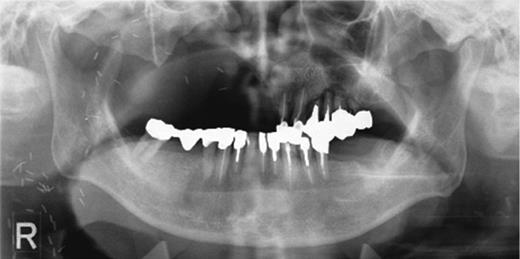

(a) The sinus cavity. A 12 × 5 mm section of bone has been removed at the maxillary sinus anterior wall with a piezoelectric instrument. There is no apparent damage of the membrane of the maxillary sinus. (b) Artificial bone has been grafted in the formed sinus cavity and placed on the alveolar bone.